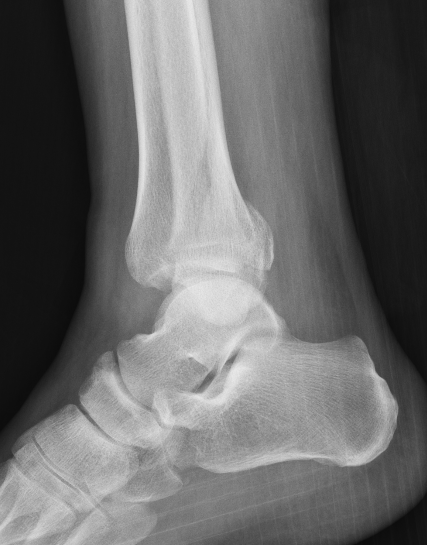

| Bimalleolar fractures | Trimalleolar fractures |

Fibular + medial malleolus Fibular + posterior malleolus |

Fibular + Medial malleolus + Posterior malleolus |

Bimalleolar fractures

Medial malleolus + Weber B lateral malleolus

Medial malleolus + Weber C lateral malleolus

Tri-Malleolar Fracture

Lateral malleolus + medial malleolus + posterior malleolus